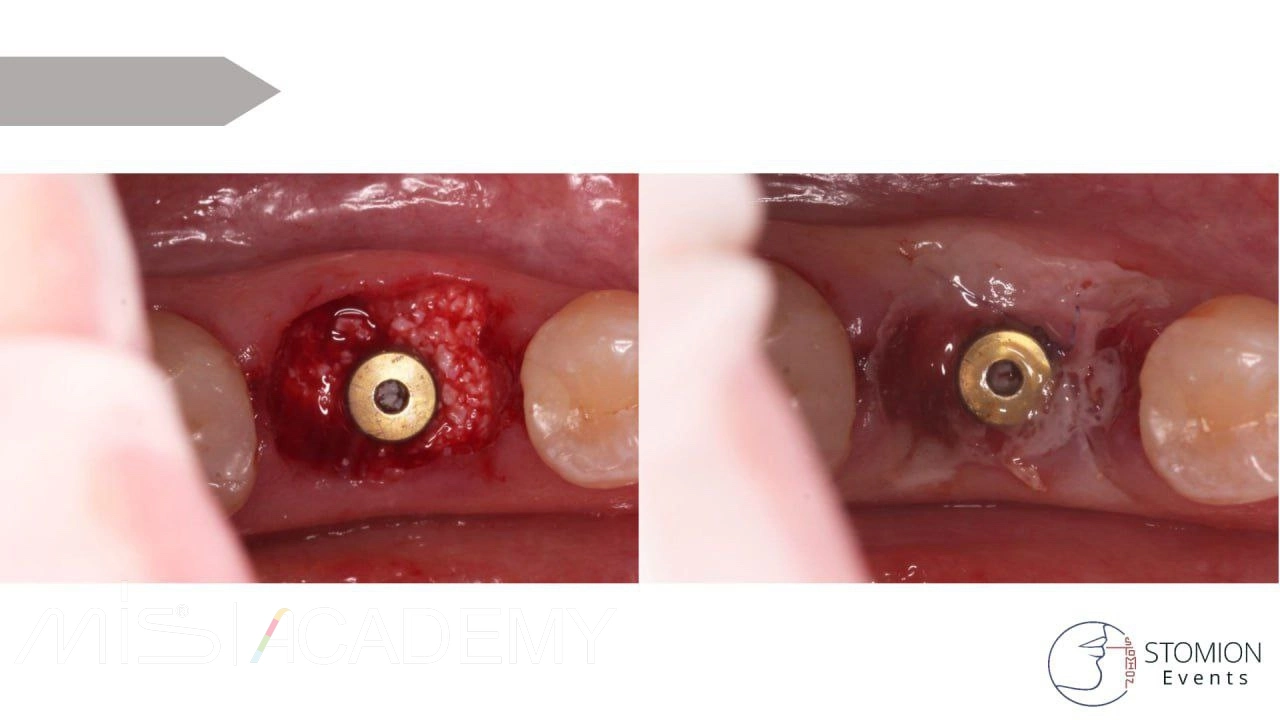

— 4.6 имплантация MIS C1 3,75х10 + connect 2мм + СТТ, фиксированный апикально к надкостнице, перекрыт расщепленным лоскутом.

Наблюдаем тенденцию образования кости вестибулярно в пришеечной зоне 4.6 — интересное наблюдение.